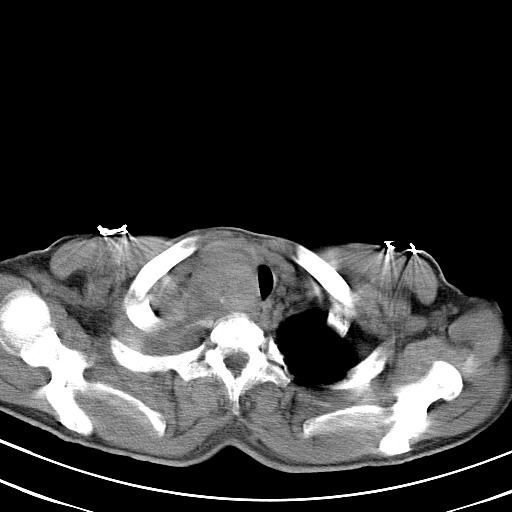

以下是引用汪涛同志在2007-8-2 0:40:00的发言:[br]病变虽然广泛,同时侵及双侧纵隔,但是无论左侧和右侧上下观察都是与右侧颈部甲状腺相延续的,而且强化幅度基本一致,又同时具有恶性病变病变的某些特征:肿块过大且密度不均,部分层面与正常纵隔结构分界不清,结合病史已有两年,考虑:胸内甲状腺肿恶变可能。[br]